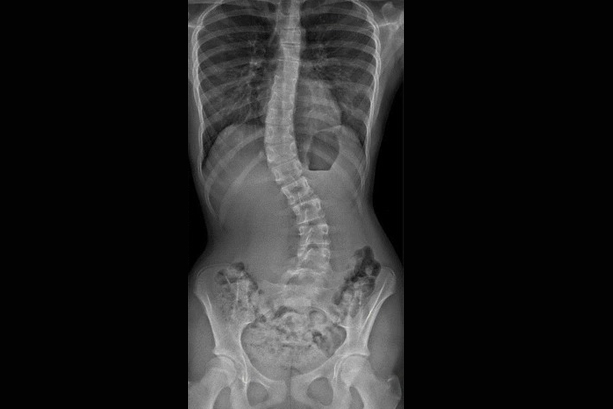

SRF TAKES PRIDE IN PRESENTING TO YOU A FEW INTERESTING CASES

More than 300 Underprivileged Patients have been Operated through our Foundation over the last 15 years !

book_4 Notable

Cases